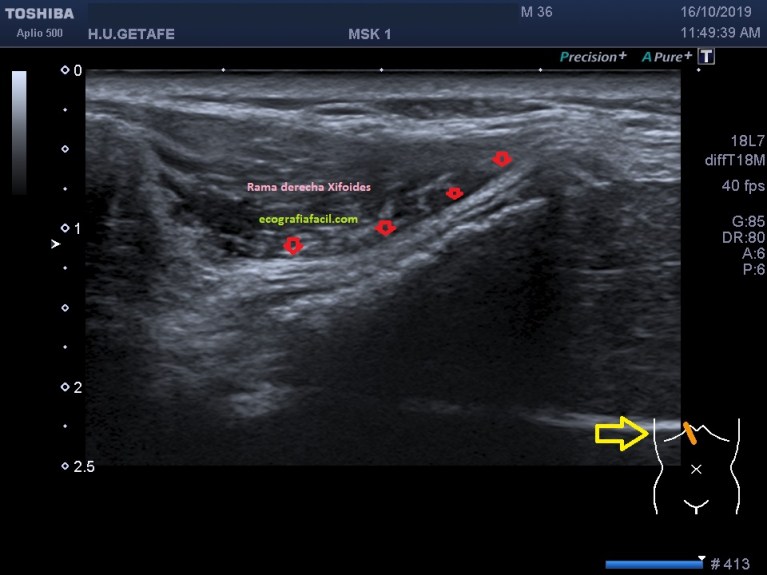

Se evidencia una imagen donde el apéndice xifoides parece terminar en dos, bífido. Lo puedes apreciar como dos imágenes hiperecogénicas señaladas con flecha rosa, a niveles distintos, la izquierda más anterior que la derecha. En el corte longitudinal de ambas terminaciones observamos esto (imagen 4 y 5)

En la imagen 4 y 5, marcado por flechas rojas, ves ambas terminaciones, observa en las imágenes la angulación de la sonda en un corte parasagital para poder ver en toda su longitud dicha terminación en cada uno de los lados.